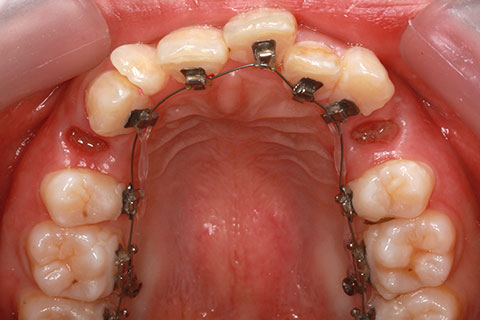

治療前

治療中(開始直後)

治療中(開始半年後)

治療後

- 年齢・性別

- 25歳女性

- 治療期間

- 2年0ヶ月

- 抜歯

- 上下4番抜歯

- 治療費

- 110万円

- 治療内容

- 施術の副作用(リスク)

- 表側矯正と比較して、力学的な操作性が複雑なため、ボーイングエフェクトを起こしやすい。